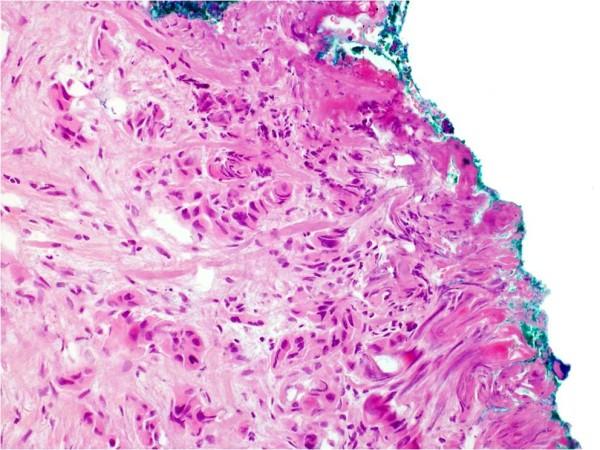

115例T1-T2期口腔鳞状细胞癌患者的临床病理参数、复发情况、局部区域及远处转移情况

Clinicopathological parameters, recurrence, locoregional and distant metastasis in 115 T1-T2 oral squamous cell carcinoma patients.

The incidence of oral squamous cell carcinoma remains high. Oral and oro-pharyngeal carcinomas are the sixth most common cancer in the world. Several clinicopathological parameters have been implicated in prognosis, recurrence and survival, following oral squamous cell carcinoma. In this retrospective analysis, clinicopathological parameters of 115 T1/T2 OSCC were studied and compared to recurrence and death from tumour-related causes. The study protocol was approved by the Joint UCL/UCLH committees of the ethics for human research. The patients' data was entered onto proformas, which were validated and checked by interval sampling. The fields included a range of clinical, operative and histopathological variables related to the status of the surgical margins. Data collection also included recurrence, cause of death, date of death and last clinic review. Causes of death were collated in 4 categories (1) death from locoregional spread, (2) death from distant metastasis, (3) death from bronchopulmonary pneumonia, and (4) death from any non-tumour event that lead to cardiorespiratory failure. The patients' population comprised 65 males and 50 females. Their mean age at the 1st diagnosis of OSCC was 61.7 years. Two-thirds of the patients were Caucasians. Primary sites were mainly identified in the tongue, floor of mouth (FOM), buccal mucosa and alveolus. Most of the identified OSCCs were low-risk (T1N0 and T2N0). All patients underwent primary resection +/- neck dissection and reconstruction when necessary. Twenty-two patients needed adjuvant radiotherapy. Pathological analysis revealed that half of the patients had moderately differentiated OSCC. pTNM slightly differed from the cTNM and showed that 70.4% of the patients had low-risk OSCC. Tumour clearance was ultimately achieved in 107 patients. Follow-up resulted in a 3-year survival of 74.8% and a 5-year survival of 72.2%. Recurrence was identified in 23 males and 20 females. The mean age of 1st diagnosis of the recurrence group was 59.53 years. Most common oral sites included the lateral border of tongue and floor of mouth. Recurrence was associated with clinical N-stage disease. The surgical margins in this group was evaluated and found that 17 had non-cohesive invasion, 30 had dysplasia at margin, 21 had vascular invasion, 9 had nerve invasion and 3 had bony invasion. Severe dysplasia was present in 37 patients. Tumour clearance was achieved in only 8 patients. The mean depth of tumour invasion in the recurrence group was 7.6 mm.An interesting finding was that 5/11 patients who died of distant metastasis had their primary disease in the tongue. Nodal disease comparison showed that 8/10 patients who died of locoregional metastasis and 8/11 patients who died from distant metastasis had clinical nodal involvement. Comparing this to pathological nodal disease (pTNM) showed that 10/10 patients and 10/11 patients who died from locoregional and distant metastasis, respectively, had nodal disease. All patients who died from locoregional and distant metastasis were shown to have recurrence after the primary tumour resection. Squamous cell carcinoma of the oral cavity has a poor overall prognosis with a high tendency to recur at the primary site and extend to involve the cervical lymph nodes. Several clinicopathological parameters can be employed to assess outcome, recurrence and overall survival.

口腔鳞状细胞癌的发病率仍然很高。口腔癌和口咽癌是全球第六大常见癌症。口腔鳞状细胞癌发生后,一些临床病理参数与预后、复发和生存率相关。在这项回顾性分析中,研究了115例T1/T2期口腔鳞状细胞癌的临床病理参数,并将其与肿瘤相关原因导致的复发和死亡情况进行比较。该研究方案已获得伦敦大学学院/大学学院医院人类研究伦理联合委员会的批准。患者数据被录入表格,并通过间隔抽样进行验证和检查。这些领域包括一系列与手术切缘状态相关的临床、手术和组织病理学变量。数据收集还包括复发情况、死亡原因、死亡日期和最后一次临床复查。死亡原因分为4类:(1) 局部区域扩散导致的死亡;(2) 远处转移导致的死亡;(3) 支气管肺炎导致的死亡;(4) 任何导致心肺功能衰竭的非肿瘤事件导致的死亡。患者群体包括65名男性和50名女性。他们首次诊断为口腔鳞状细胞癌时的平均年龄为61.7岁。三分之二的患者为白种人。原发部位主要位于舌、口底、颊黏膜和牙槽。大多数确诊的口腔鳞状细胞癌为低风险(T1N0和T2N0)。所有患者均接受了原发灶切除,必要时进行颈部清扫和重建。22例患者需要辅助放疗。病理分析显示,一半的患者患有中度分化的口腔鳞状细胞癌。pTNM与cTNM略有不同,显示70.4%的患者患有低风险口腔鳞状细胞癌。最终107例患者实现了肿瘤清除。随访结果显示3年生存率为74.8%,5年生存率为72.2%。23名男性和20名女性出现复发。复发组首次诊断时的平均年龄为59.53岁。最常见的口腔部位包括舌外侧缘和口底。复发与临床N分期疾病相关。对该组的手术切缘进行评估,发现17例有非粘连性浸润,30例切缘有发育异常,21例有血管浸润,9例有神经浸润,3例有骨浸润。37例患者存在重度发育异常。仅8例患者实现了肿瘤清除。复发组肿瘤浸润的平均深度为7.6毫米。一个有趣的发现是,11例死于远处转移的患者中有5例原发疾病位于舌部。淋巴结疾病比较显示,10例死于局部区域转移的患者中有8例以及11例死于远处转移的患者中有8例有临床淋巴结受累。将此与病理淋巴结疾病(pTNM)进行比较显示,分别死于局部区域和远处转移的10例患者和11例患者中有10例有淋巴结疾病。所有死于局部区域和远处转移的患者在原发肿瘤切除后均出现复发。口腔鳞状细胞癌总体预后较差,在原发部位复发和累及颈部淋巴结的倾向较高。可以采用一些临床病理参数来评估预后、复发和总体生存率。